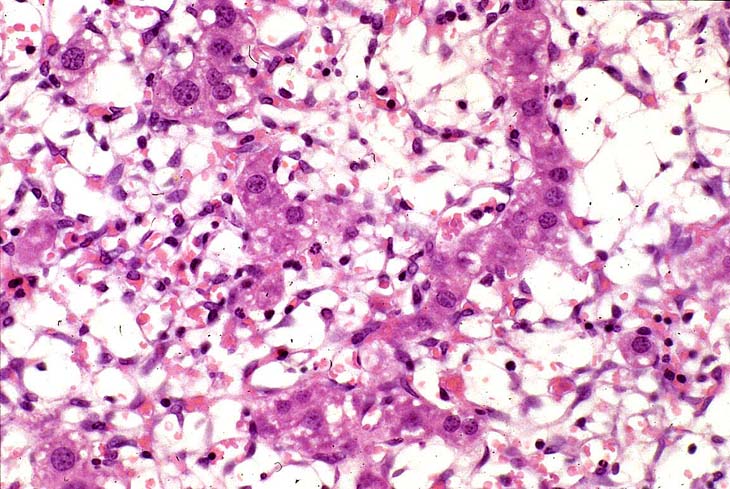

A relative discrete Ito cell tumor is present within this hepatic lobe; a higher magnification shows proliferation of stellate cells within the hepatic sinusoidal spaces.

This Ito cell tumor is comprised of a mixture of stellate cells and mature adipocytes.